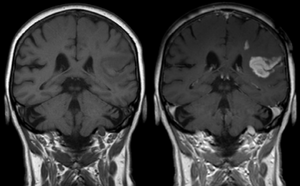

وسط تباين في التصوير بالرنين المغناطيسي

الأدوات الملوِّنة في التصوير بالرنين المغناطيسي هي مجموعة من المواد الملوِّنة التي تستخدم لتحسين الرؤية لمكونات الجسم الداخلية في التصوير بالرنين المغناطيسي(MRI)[1]. أكثر المركبات إستخداماً في تحسين التباين هي المرتكزة على "الجادلينيوم Gd". مثل هذه المواد الملونة تعمل على تقصير "وقت الاسترخاء" للأنوية في أنسجة الجسم تبعاً لإعطائها فموياً أو بالوريد. في أجهزة الرنين المغناطيسي، المقاطع من الجسم التي تتعرض لمجال مغناطيسي قوي جداً تسبب تأين -بالدرجة الأولى - لنويات الهيدروجين من جزيئات الماء في الانسجة في اتجاه المجال المغناطيسي. موجة تردد راديوية مكثفة تُسلَّط والتي بدورها تجعل المجال المغناطيسي الذي نشأ من نويّات الهيدروجين يَميل باتجاه اسلاك الاستقبال حيث ذرات الهيدروجين المُأيَّنة يُكشف عنها.التذبذب العشوائي الدوراني يطابق التردد الرنيني لنويّات الهيدروجين فتزودها "بالاسترخاء" التي تجمع المحصلة المغناطيسية لنويّات الهيدروجين وتُعيدها لوضع الاتزان بمحاذاة المجال المغناطيسي. كميّة التأين للنويّات يتم الكشف عنها باستخدام أجهزة الاستقبال التي تستخدمها لإنشاء صورة رنين مغناطيسي لكن الانحلال الثابت مع الوقت يعرف بـ وقت الاسترخاء "T1". بروتونات الماء في الانسجة المختلفة لديها قيم وقت استرخاء مختلفة، وهذا هو واحد من أهم الأسباب لوجود التباين في صورة الرنين المغناطيسي. المادة الملونة عادةً تُقصِّر وقت الاسترخاء، ولكن في بعض الحالات تزيده، قيم ال "T1" في جزيئات الماء القريبة من المادة الملونة تختل وبالتالي زيادة التباين في الصورة.

Gadolinium(III) containing MRI contrast agents (often termed simply "gado" or "gad") are the most commonly used for enhancement of vessels in MR angiography or for brain tumor enhancement associated with the degradation of the blood–brain barrier. For large vessels such as the aorta and its branches, the gadolinium(III) dose can be as low as 0.1 mmol per kg body mass. Higher concentrations are often used for finer vasculature.[2] Gd(III) chelates do not pass the intact blood–brain barrier because they are hydrophilic. Thus, these are useful in enhancing lesions and tumors where blood-brain barrier is compromised and the Gd(III) leaks out. In the rest of the body, the Gd(III) initially remains in the circulation but then distributes into the interstitial space or is eliminated by the kidneys. Gadolinium-based contrast agents appear to be safe in pregnancy.[3]